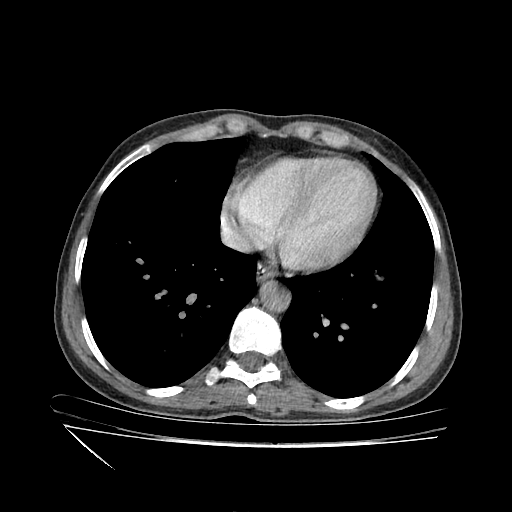

Generated VENOUS CT scan (A→B translation)

Full window (WL 1023.5, WW 4095 β†’ Low βˆ’1024, High +3071)

Lung window (WL -600, WW 1500 β†’ Low βˆ’1350, High +150)

Mediastinum window (WL 40, WW 400 β†’ Low βˆ’160, High +240)

Targeted Slice 70 - Mediastinum Window Analysis (Generated vs Real Venous)

0.805

Mediastinum SSIM

38.0

Mediastinum RMSE

12.5

Mediastinum MAE